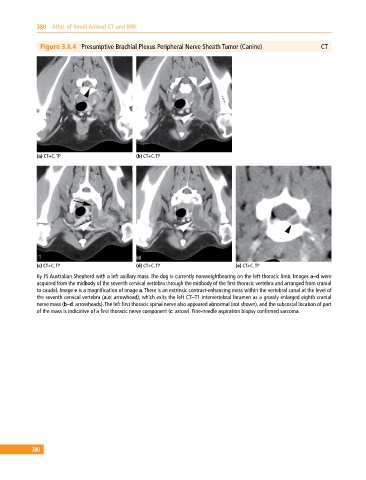

Figure 3.6.4 Presumptive Brachial Plexus Peripheral Nerve Sheath Tumor (Canine) CT

6y FS Australian Shepherd with a left axillary mass. The dog is currently nonweightbearing on the left thoracic limb. Images a–d were

acquired from the midbody of the seventh cervical vertebra through the midbody of the first thoracic vertebra and arranged from cranial

to caudal. Image e is a magnification of image a. There is an extrinsic contrast‐enhancing mass within the vertebral canal at the level of

the seventh cervical vertebra (a,e: arrowhead), which exits the left C7–T1 intervertebral foramen as a grossly enlarged eighth cranial

nerve mass (b–d: arrowheads). The left first thoracic spinal nerve also appeared abnormal (not shown), and the subcostal location of part

of the mass is indicative of a first thoracic nerve component (c: arrow). Fine‐needle aspiration biopsy confirmed sarcoma.